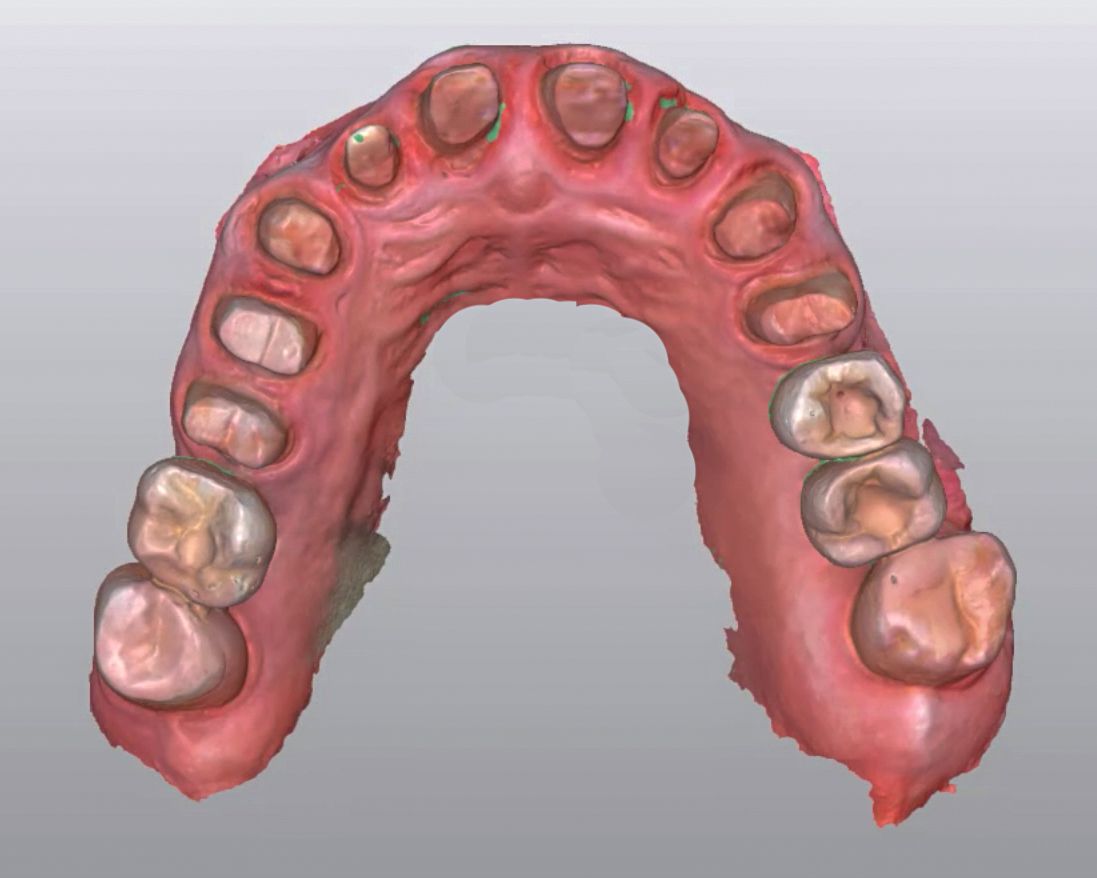

At the next appointment, the patient came to the clinic early in the morning. All old crowns were removed, and teeth 24, 25 and 34 were prepared for crowns. Intraoral data were acquired with the new Straumann Virtuo Vivo™ intraoral scanner, and a picture of the patient’s face was taken.

STL files of the digital wax-up, teeth preps, and the patient’s picture were uploaded to the Straumann CARES® Visual software, and crowns were designed. After 25 minutes, all the crowns were sent to be milled with the Straumann C series milling machine. On completion of the milling process, all the crowns were placed for a final fit check (Figs. 9-13).